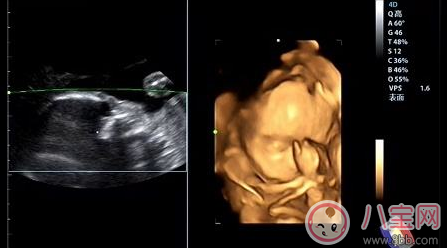

四維彩超采用新式的高清攝像儀,圖像是立體的,更清晰,并能夠多方位、多角度地觀察宮內胎兒的生長發育情況,為早期診斷胎兒先天性體表畸形和先天性心臟疾病提供準確的科學依據。四維彩超不僅可以測定胎兒胎齡,還可以對胎兒的身體發育情況、心肺功能情況、是否有唇腭裂等進行準確的排查,而這些,是普通B超所做不到的。

系統彩超就是應用高分辨率的彩色多普勒血流顯像儀對胎兒全身做系統的檢查,檢查的內容包含胎兒的脊椎、頭顱、顏面部、心臟、腹部(胃、肝、腎、膀胱)、肢體等。出來的圖像是斷面,一般人看不懂,對B超醫師的技術要求較高,出來的圖像只有他們能看懂。檢查的比較詳細,全身各個系統基本都要檢查,檢查的時間長;而四維彩超有針對性,比如你想看孩子面部的發育情況,四維彩超要看的清楚。

四維彩超可立體顯示胎兒的顏色、面、各器官的發育情況,甚至胎兒在母體里的狀態也可以觀察到;對胎兒畸形,如唇裂、腭裂、骨骼發育異常、心血管畸形等能早期診斷。了解胎兒宮內動態的一個胎動過程,再者動態攝錄胎兒宮內資態,可以讓孕媽媽看到胎兒一連串的動作,所以四維看起來會更清楚明了,還可以留作永久的紀念。三維彩超只能是某個時間點上的照片,四維彩超的就可以做成DV那樣連續的,可以刻錄光盤。而且四維彩超不存在射線、光波和電磁波等方面的輻射,對人體的健康沒有任何影響,現今醫學上并沒有對人體的健康有任何影響的報道。